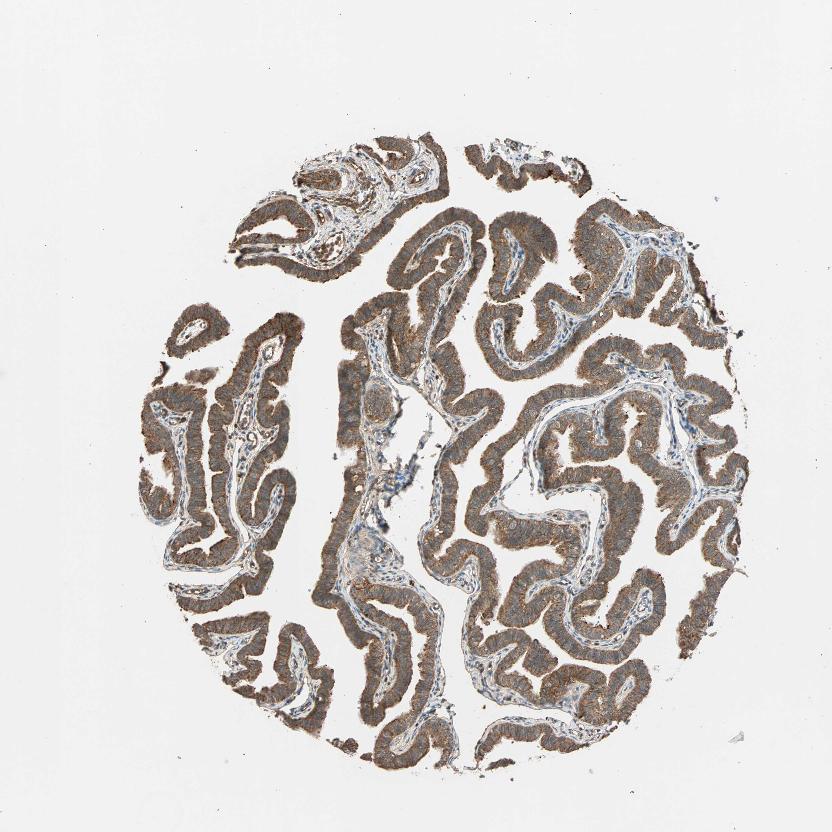

TISSUE PRIMARY DATA FALLOPIAN TUBE Show tissue menu

FALLOPIAN TUBE - Antibody stainingi

Antibody staining in the annotated cell types in the current human tissue is reported as not detected, low, medium, or high, based on conventional immunohistochemistry profiling in selected tissues. This score is based on the combination of the staining intensity and fraction of stained cells.

Each image is clickable and will lead to virtual microscopy that enables deeper exploration of all samples and also displays staining intensity scores, fraction scores and subcellular localization as well as patient and tissue information for each sample.

Antibody HPA003995Antibody HPA005700Antibody HPA030069Antibody CAB002683

Glandular cells MediumHighLowHigh